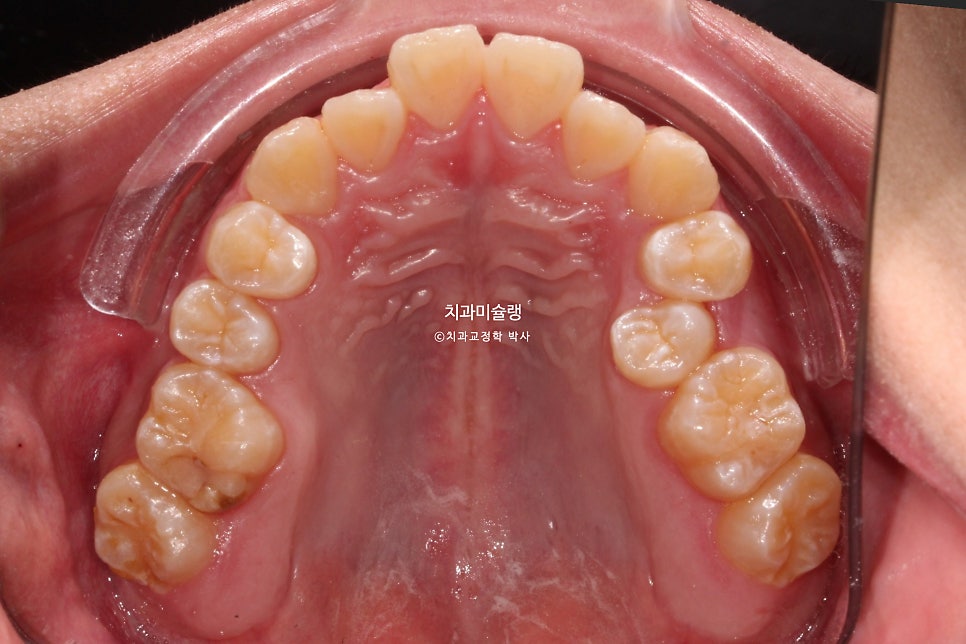

앞니에 약간의 개방교합이 보이고

앞니가 거꾸로 물리는 반대교합입니다.

치아만 거꾸로 물리는에 아닌, 골격성 3급 부정교합으로 양악수술이 필요한 주걱턱 입니다.

어금니도 마찬가지로 3급 교합관계를 보입니다.